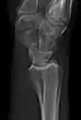

AP and lateral elbow X-ray

• Elbow - AP and Lateral. Radial head projections available on request